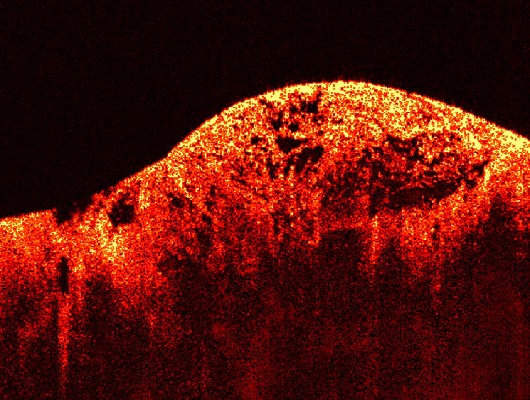

En definitiva, son un tipo de cáncer que se origina en los tejidos blandos (músculos, grasa, vasos sanguíneos, nervios, tendones, ligamentos y otros tejidos conectivos) o en los huesos. A diferencia de los carcinomas (que se originan en células que recubren órganos o glándulas, como la piel o el revestimiento intestinal), los sarcomas son de origen mesenquimal.

• De tejidos blandos: Liposarcoma (en el tejido graso), leiomiosarcoma (en el músculo liso), angiosarcoma (en los vasos sanguíneos), sarcoma sinovial, histiocitoma fibroso maligno (ahora más conocido como sarcoma pleomórfico indiferenciado), entre otros. Pueden aparecer en cualquier parte del cuerpo, aunque son más comunes en las extremidades, el tronco y el retroperitoneo (detrás del abdomen).